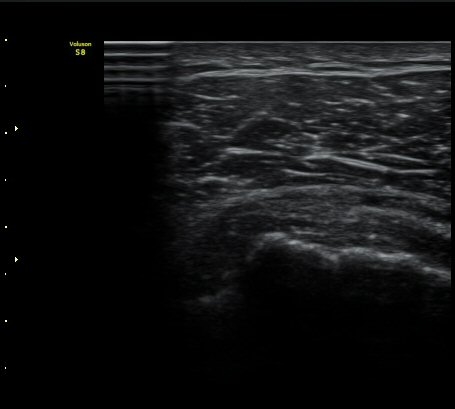

°ß°©ÇÏ±Ù°Ç »óºÎ Á¾´Ü¸é°Ë»ç»ó ¼Ò°áÀýÀÇÇÇÁú°ñÀÇ ºÒ±ÔÄ¢º¯È­¿Í °ß°©ÇÏ±Ù°Ç ¿¬°á¼º ¼Ò½ÇÀÌ

°üÂûµÊ(±×¸² 6, 7).